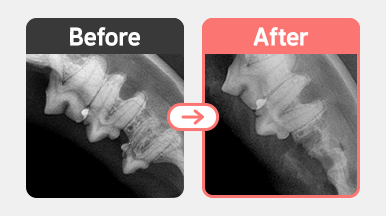

치과센터

치주염

치아흡수성병변